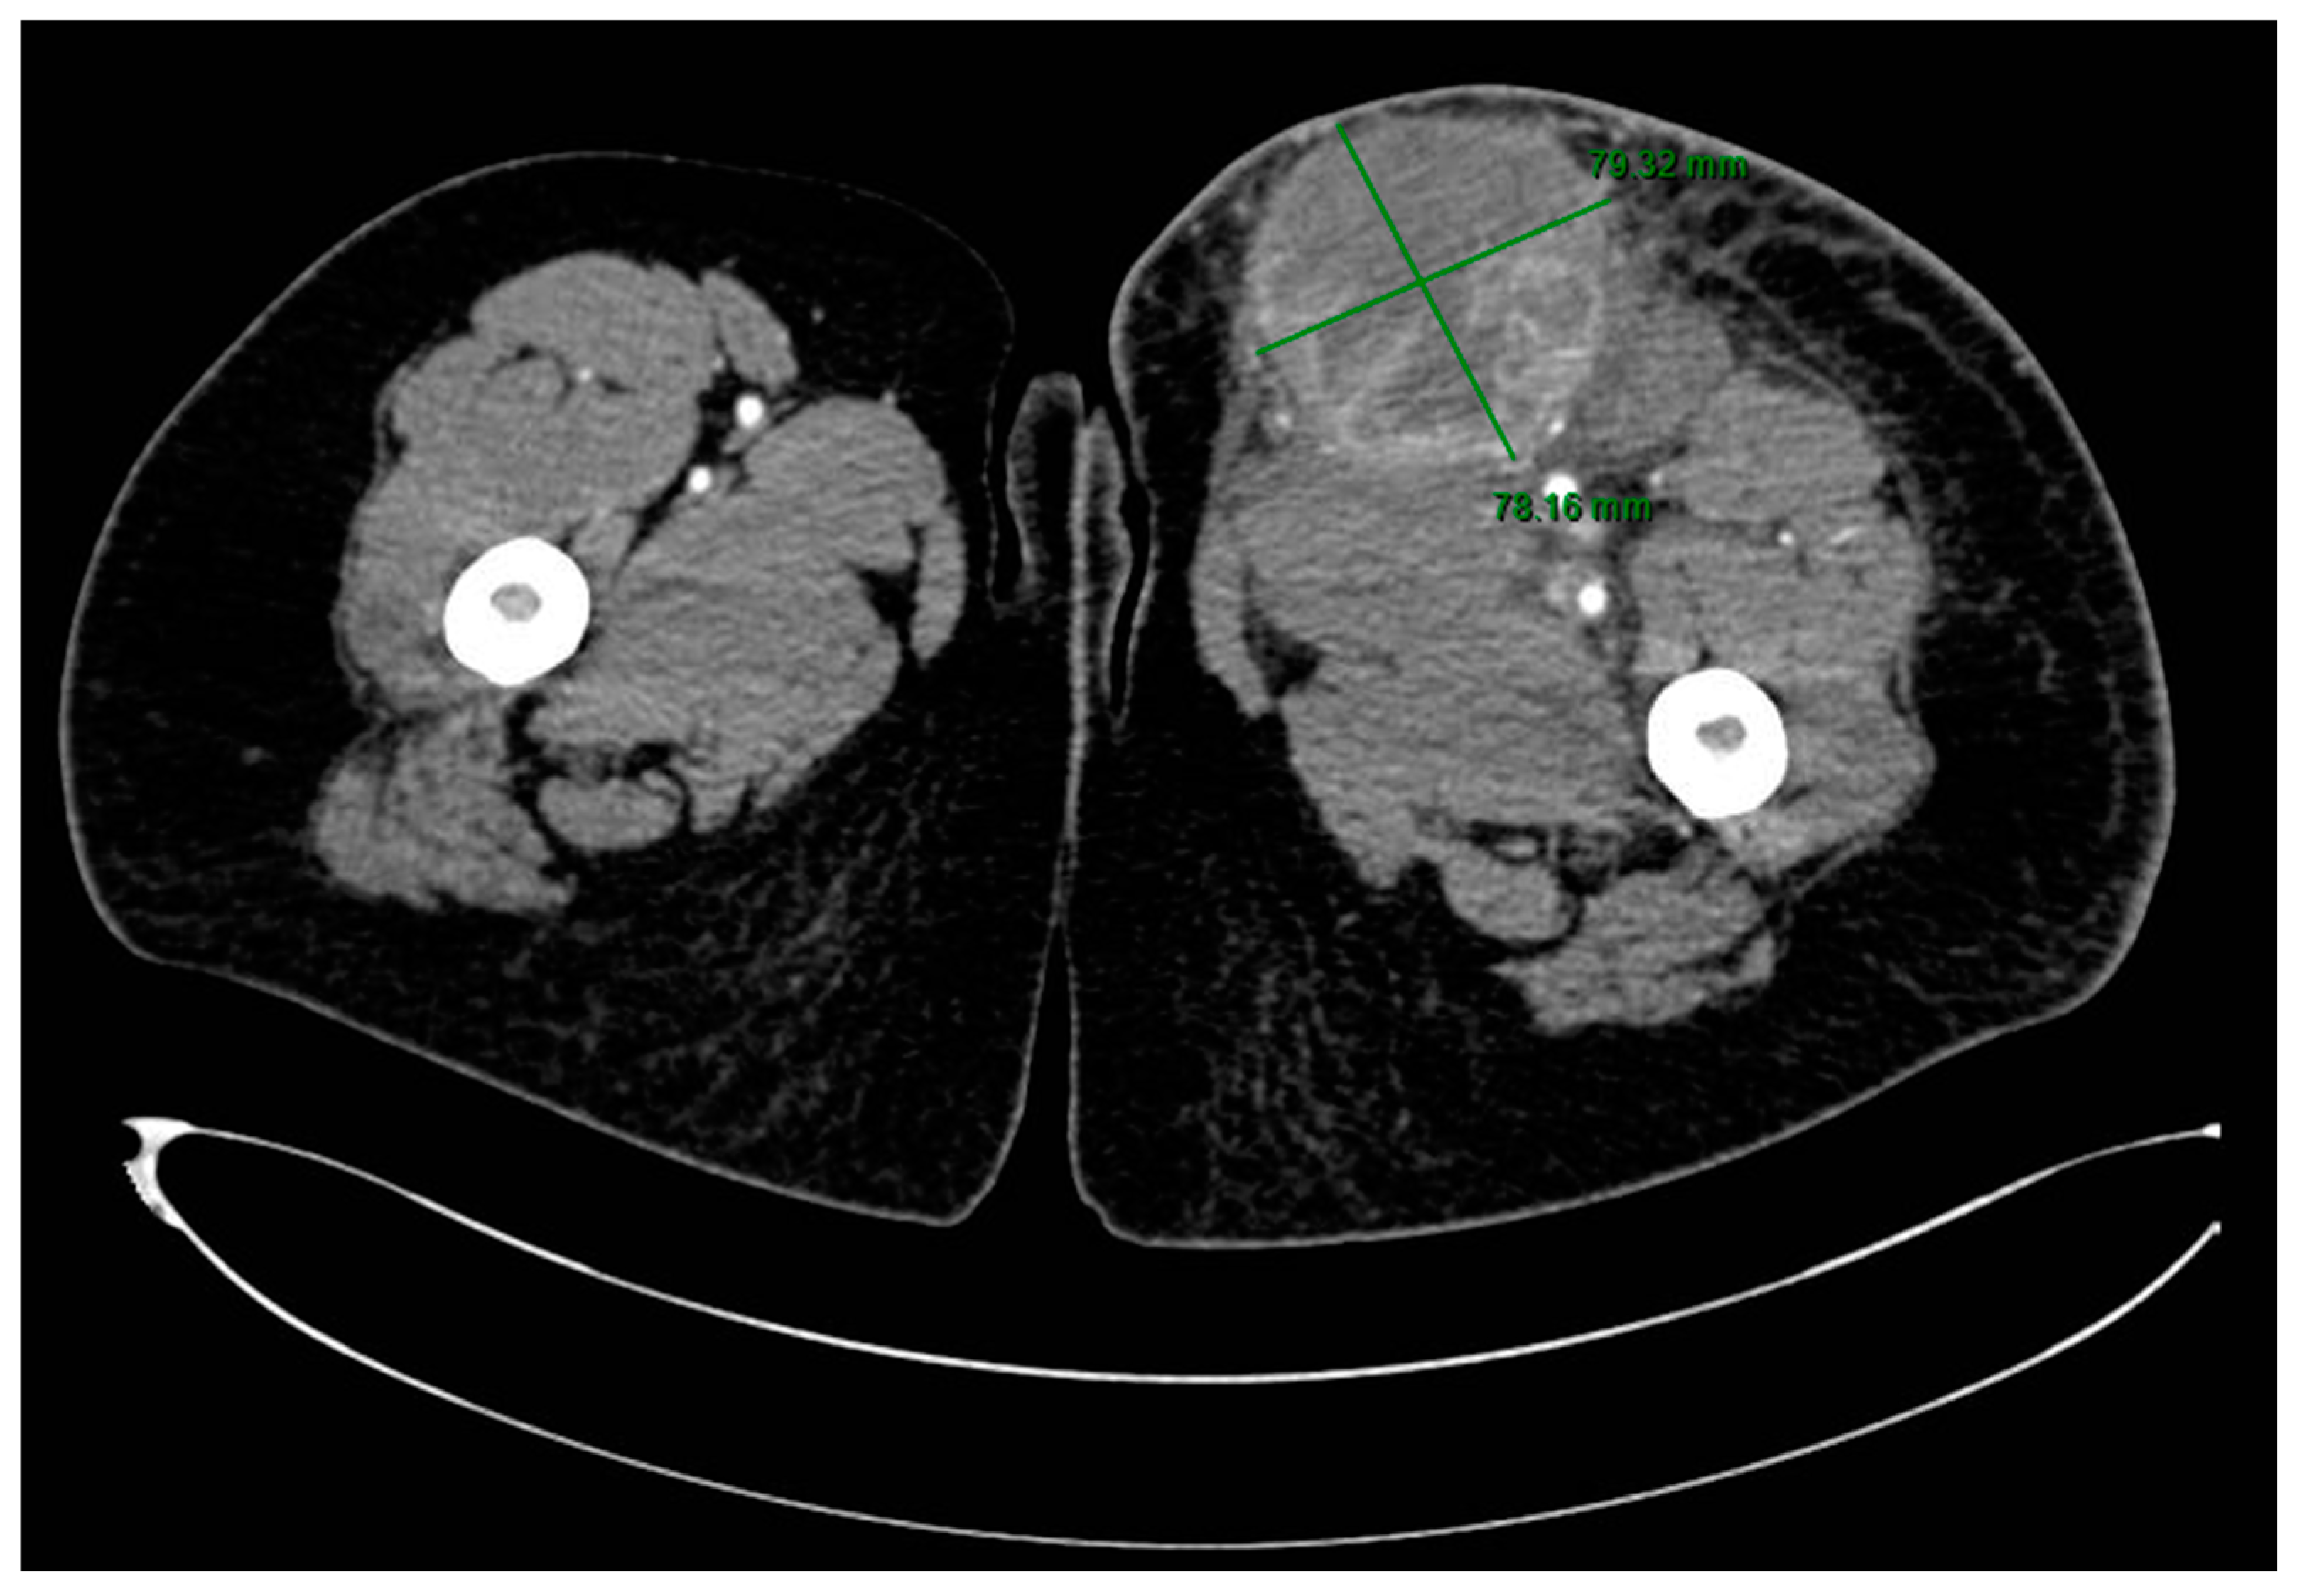

2. Case Presentation